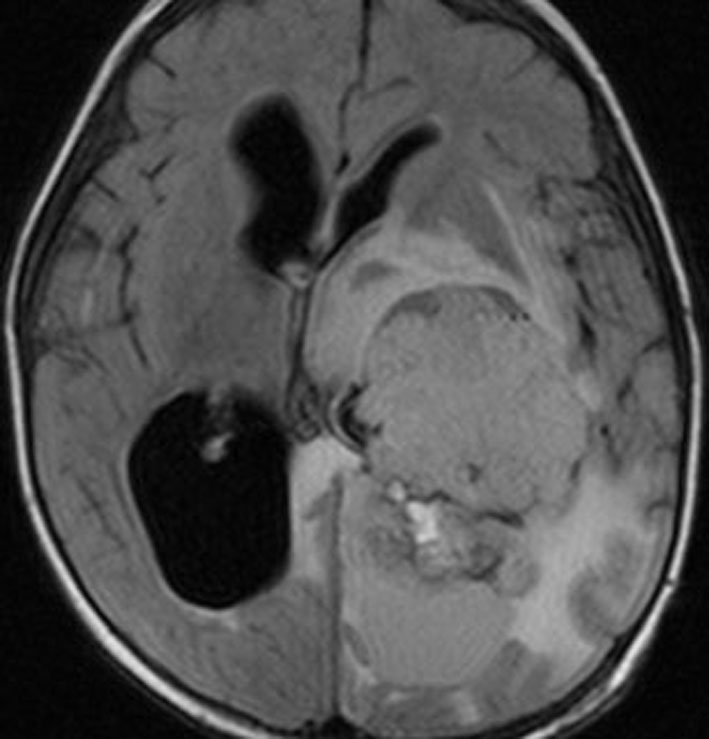

1歳児の巨大な脈絡叢乳頭腫です。このくらいのサイズになると手術で出血死することもあります。右側の画像は手術後のMRIで幸い全摘出できています。乳幼児のこのように巨大なものでは無理して全摘出にいどまないで,シャントをして水頭症を改善して,化学療法で腫瘍を小さくしてから,開頭手術するという方法もあるでしょう。執刀医の経験値で判断は異なります。